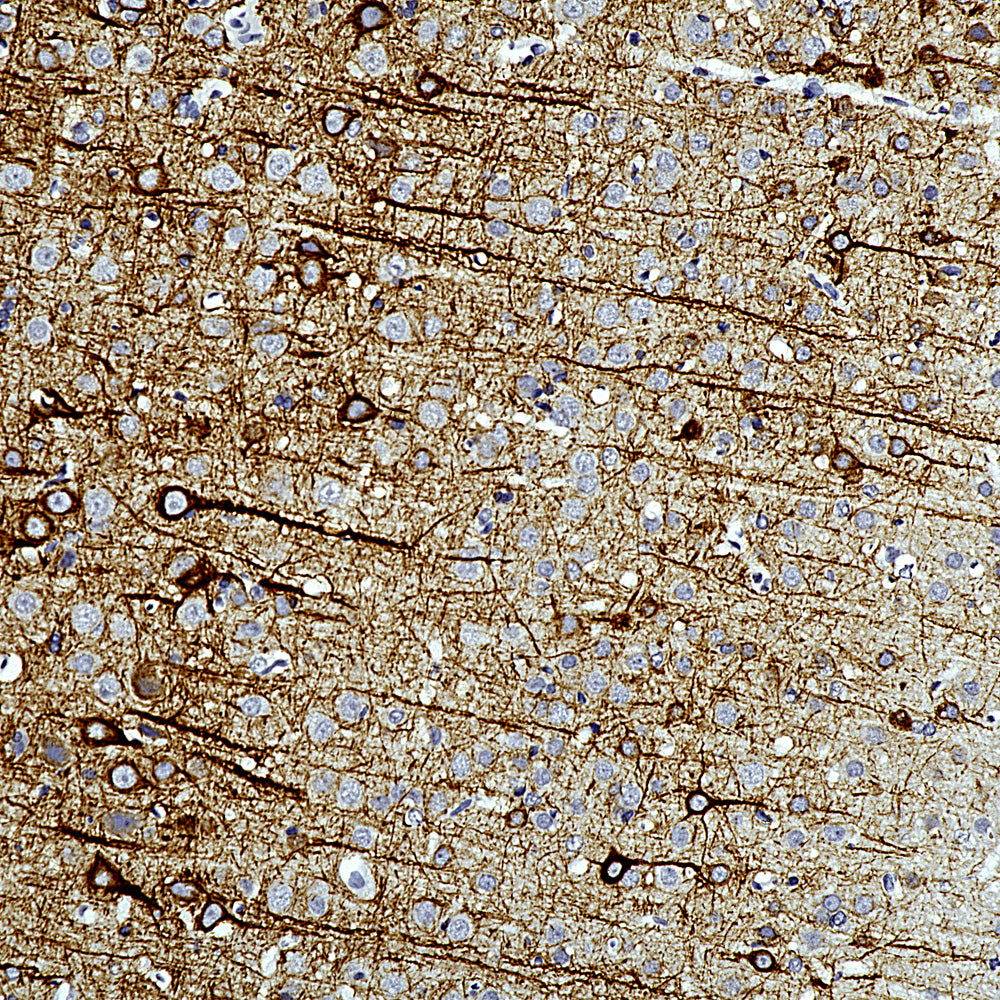

Chromogenic Immunostaining of a formalin fixed paraffin embedded brain stem section from a transgenic mouse model of ALS stained with mouse mAb to NF-L, MCA-1B11, dilution 1:1,000, detected with DAB (brown) following the Vector Labs mouse on mouse (MOM) method, without the antigen retrieval step. Hematoxylin (blue) was used as the counterstain. The MCA-1B11 antibody labels what are clearly degenerated axons, showing typical swollen, sinusoidal and discontinuous profiles. Note that under these conditions healthy axons are not stained. Mouse select image for larger view.